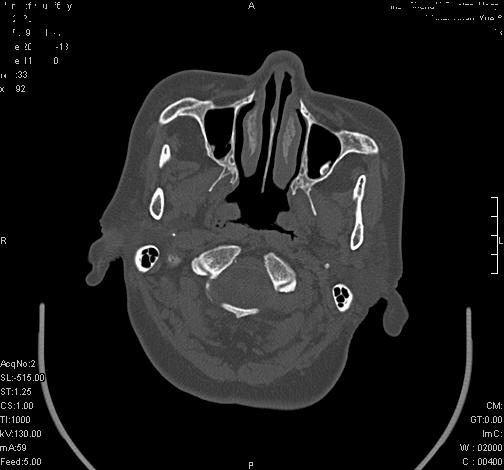

上次发的片子,不够细微。误导了大家,请大家再重新看一下,思路会更清晰。

双侧上颌窦上部黏膜明显增厚、窦腔缩小,偏后侧窦壁骨质毛糙、模糊,窦腔内见条块状钙化。结合双侧鼻甲黏膜明显增厚,以及临床症状,

考虑:双侧上颌窦霉菌性鼻窦炎

双侧上颌窦密度增高,粘膜增厚,内见条片状钙化,窦壁无增生与破坏征象,双侧鼻甲粘膜肥厚.

意见:双侧霉菌性上颌窦炎.

温习:真菌性鼻旁窦ct特征 1)非侵袭性病变者可涉及到鼻腔和鼻窦,多为单侧,上颌窦最多见.2)ct示窦腔内软组织增生影,可呈息肉状,+c可强化3)增生软组织影内可见散在斑片状或沙砾状钙化区,此为其典型特点,4)

非侵袭性病变可见窦壁骨质增生,破坏少见;侵袭性病变可见窦壁骨质破坏.

如此好的机器,为何不来点冠状面和失状面重建的图象呢,或许会提供更多的信息供大家参考。